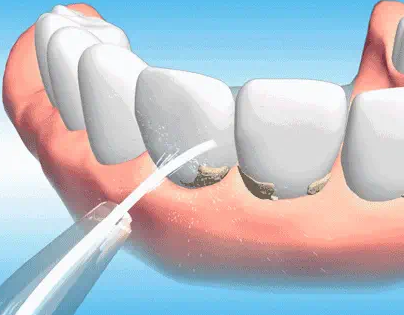

误吞少量洗牙水无需过度紧张,可先做应急处理:10分钟内用温清水漱口3-5次清理口腔残留,再喝200-300ml35-40℃温白开稀释代谢,轻微不适可用淡盐水漱口。正规口腔机构的洗牙水多为低浓度抑菌液或生理盐水,少量误吞(通常不足50ml)对健康人群无明显伤害,仅肠胃病患者可能短暂不适,1-2天可自行缓解。缓解可喝温牛奶、小米粥护黏膜,避免辛辣过烫食物,做好口腔护理并适量补水。若在非正规机构洗牙、误吞量大、出现严重过敏或特殊人群不适,需及时就医,建议选正规机构并配合操作减少误吞。